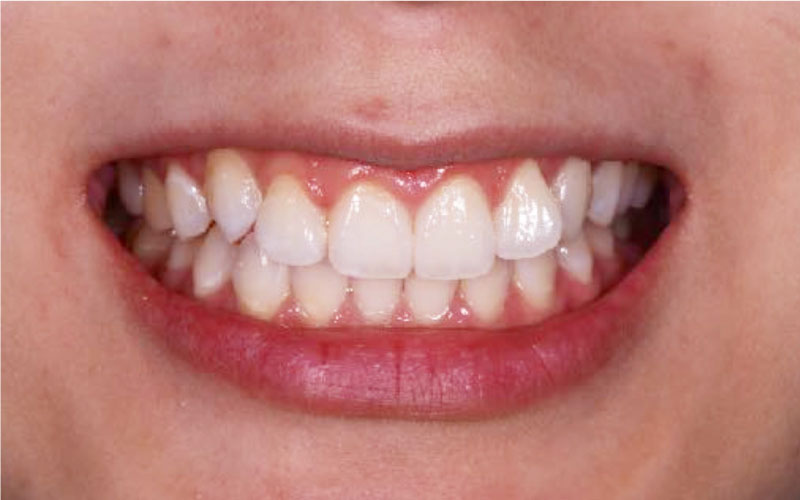

Before

• 牙齒暗黃

• 顏色不均

After

• 晶鑽居家美白

• 溫和美白不敏感

• 客製化專屬牙脫